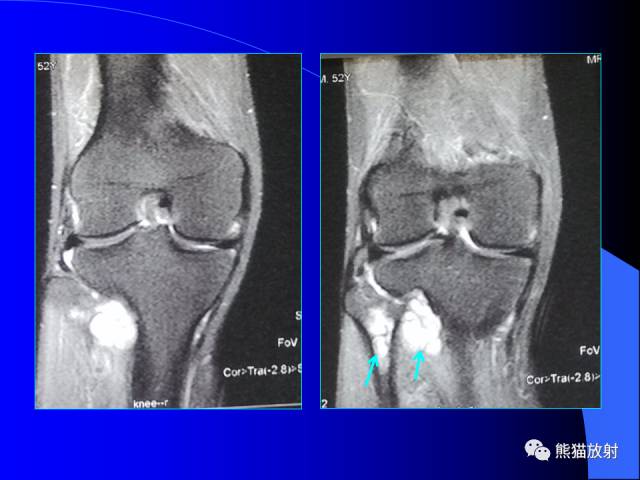

膝关节周围囊肿是较常见的病变,可以是原发的,多见于青年及儿童,囊内容物通常是黏液;也可以是继发的,多与关节腔相通,内含一般黏性的滑液,常继发于膝关节骨关节炎、类风湿关节炎、非特异性滑膜炎、半月板损伤、髌骨软骨软化症等。

腘窝囊肿是膝关节周围最常见的囊肿。